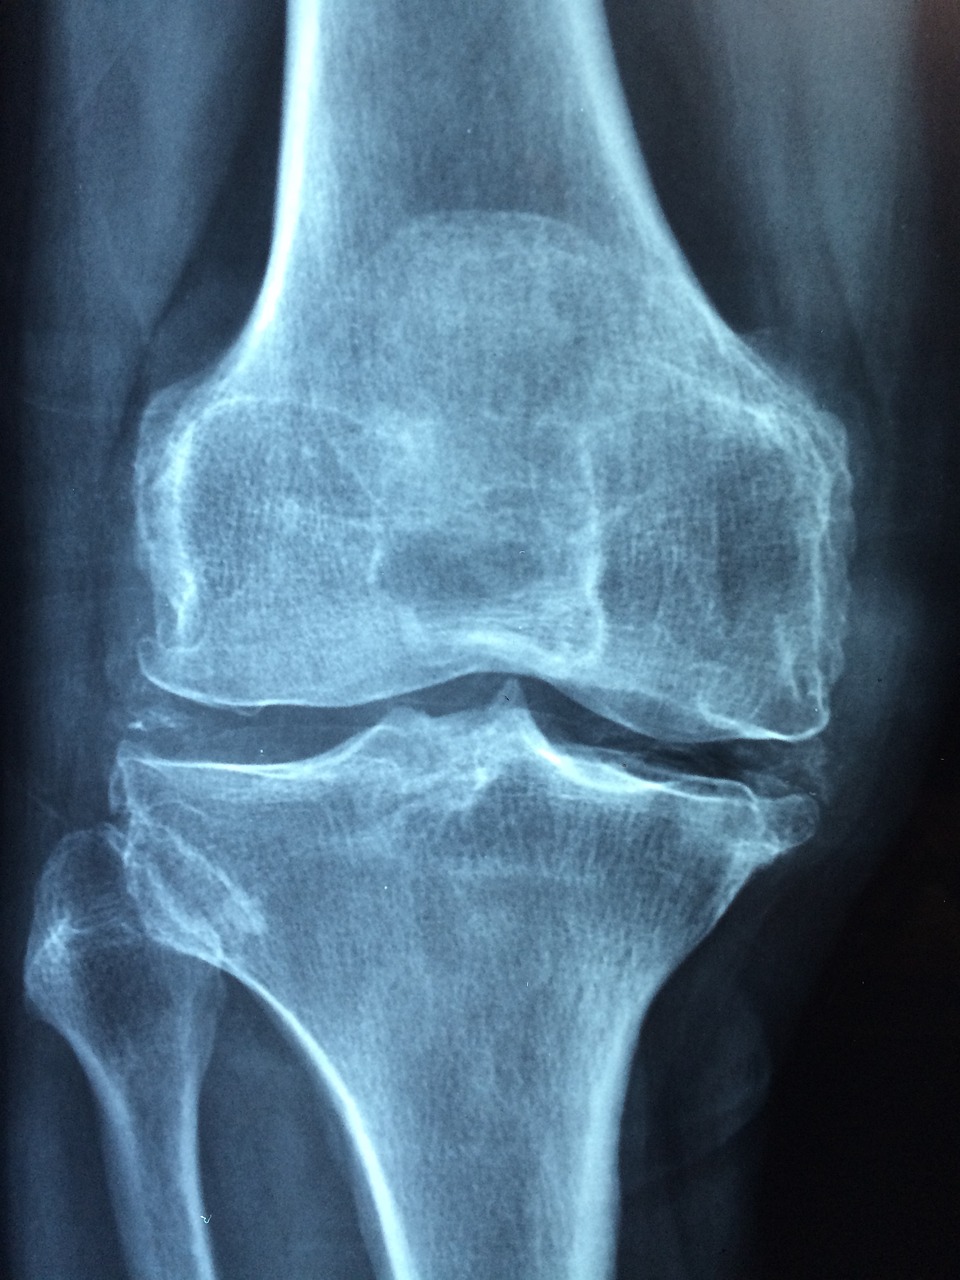

- 첫째로, 무릎 관절에서 윤활제인 관절액이 생기면서 발생하는 소리입니다. 이 관절액은 뼈와 뼈 사이의 마찰을 줄여주는 역할을 합니다. 하지만 가끔씩 소리가 날 때, 관절액 안에 포함된 기체가 작은 방울로 형성되어 터지는 것이 원인이 될 수도 있습니다.

- 둘째로, 무릎 주변의 인대, 건 및 근육이 움직일 때에도 소리가 발생할 수 있습니다. 이런 소리는 크게 두 가지로 나눌 수 있는데, 하나는 인대가 무릎 관절을 넘어갈 때 발생하는 '끝소리'이고, 다른 하나는 근육이 무릎 관절 주변에서 움직일 때 발생하는 '마찰음'입니다.